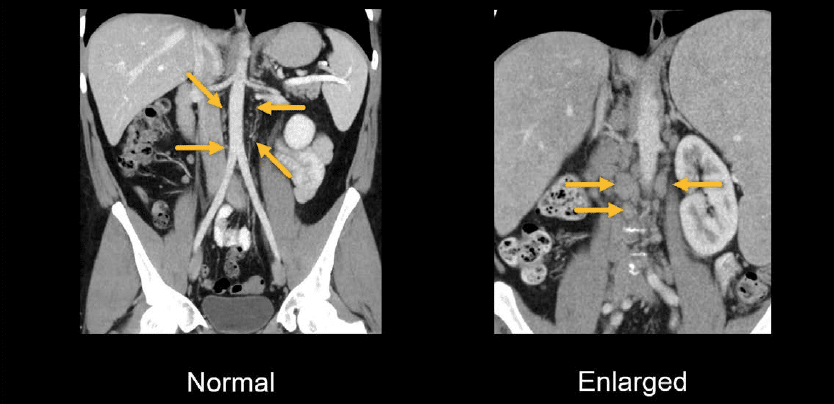

Abdominal CT: Lymph Nodes • LITFL • Radiology Library

litfl.com

litfl.com

Abdominal CT: Lymph Nodes • LITFL • Radiology Library

litfl.com

litfl.com